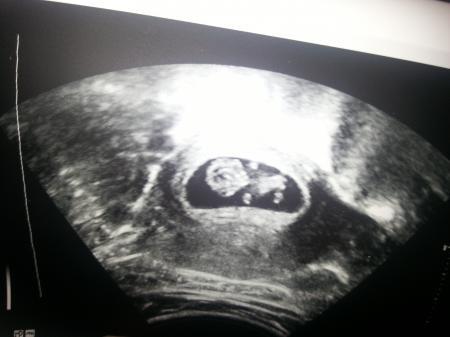

Danke euch. Hier auch noch das aktuelle Foto vom Würmchen. Sieht fast ein bisschen so aus, als würde es zeigen. :D

Bild zu